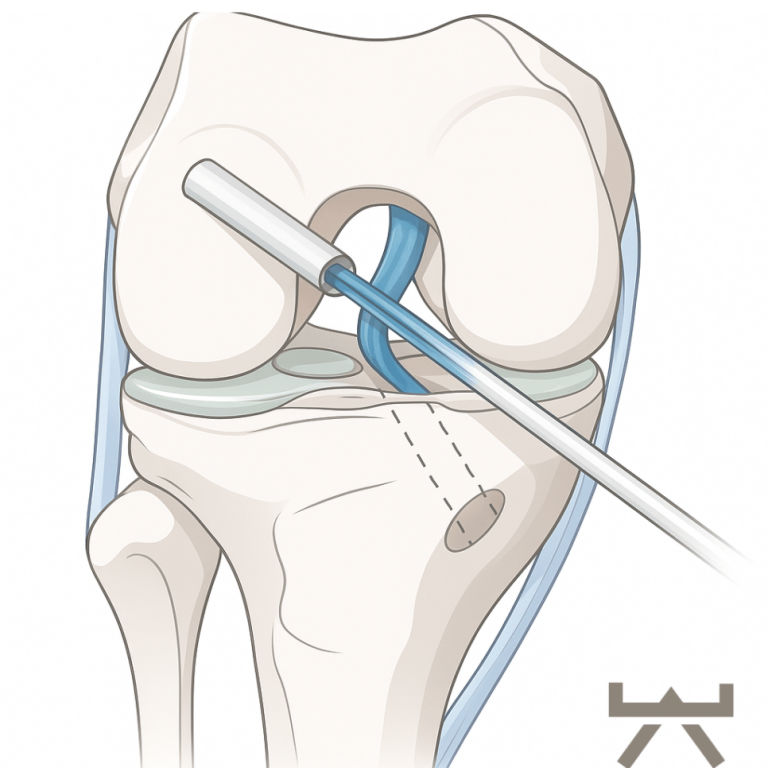

OPERATIONSARTEN

Während der Kreuzbandplastik wird das vorderste Kreuzband durch körpereigenes Sehnengewebe ersetzt. In den meisten Fällen findet die Operation arthroskopisch (mittels einer Gelenkspiegelung) statt. Als Transplantat für das Kreuzband werden vom Patienten entweder Teile der Beugesehnen (Semitendinosus-/Gracilis Sehne), oder das mittlere Drittel der Kniescheibensehne (Patellarsehne unterhalb der Kniescheibe oder Quadriceps Sehne oberhalb der Kniescheibe) entnommen. In seltenen Fällen ist ein Allograft (Spendersehne) oder ein Ersatz aus Synthetik Material notwendig. Es werden Bohrkanäle durch den Unterschenkel- und den Oberschenkelknochen vorgenommen, durch die das Transplantat dann durchgezogen und anschließend befestigt wird.

Bohrkanäle

Transplantatdurchzug